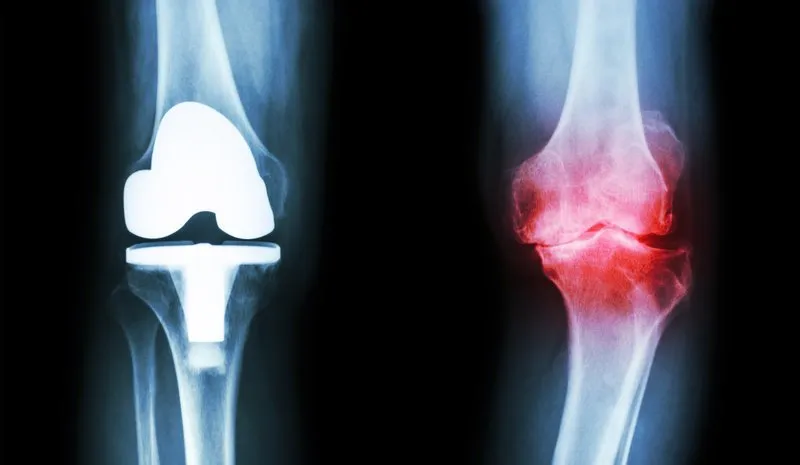

Zdjęcia rentgenowskie są podstawowym narzędziem diagnostycznym, które pozwala na ocenę struktury kości w stawach. Dzięki nim można wykryć zmiany, takie jak zwężenie przestrzeni stawowej czy obecność osteofitów. Rezonans magnetyczny (MRI) natomiast oferuje szczegółowe obrazowanie tkanek miękkich, co jest niezwykle pomocne w ocenie chrząstki, więzadeł i mięśni. Tomografia komputerowa (TK) dostarcza jeszcze bardziej szczegółowych informacji, szczególnie w przypadku skomplikowanych urazów stawów.

X-ray: Jakie zmiany wykrywa zdjęcie rentgenowskie stawów?

Zdjęcia rentgenowskie stawów są jedną z podstawowych metod diagnostycznych w ocenie chorób zwyrodnieniowych. X-ray pozwala na wykrycie istotnych zmian w strukturze stawów, takich jak zwężenie przestrzeni stawowej, co może wskazywać na postępującą degenerację. Dodatkowo, na zdjęciach rentgenowskich można zaobserwować obecność osteofitów, czyli wyrostków kostnych, które często pojawiają się w wyniku przewlekłego stanu zapalnego. Choć zdjęcia rentgenowskie są pomocne w ocenie stopnia zaawansowania choroby, mogą nie wykrywać wczesnych zmian, które są widoczne w bardziej zaawansowanych badaniach obrazowych.